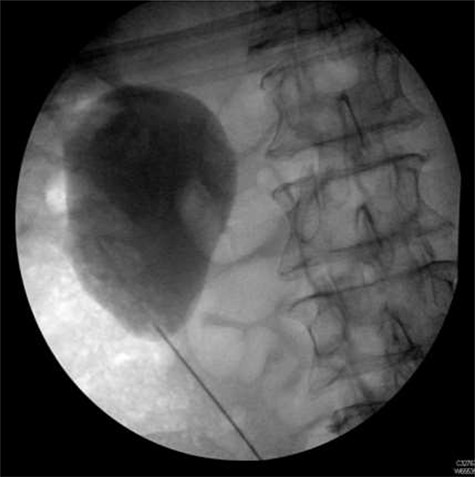

Following completion of chemotherapy, 12 weeks after stent insertion, the patient attended clinic for stent removal however, the stent could not be visualized on flexible cystoscopy. An abdominal X-ray showed proximal migration of the stent with the proximal end of the stent appearing to wrap around the aforementioned staghorn calculus (Fig. 4).

Plain abdominal X-ray performed at follow-up demonstrating proximal ureteric stent migration.